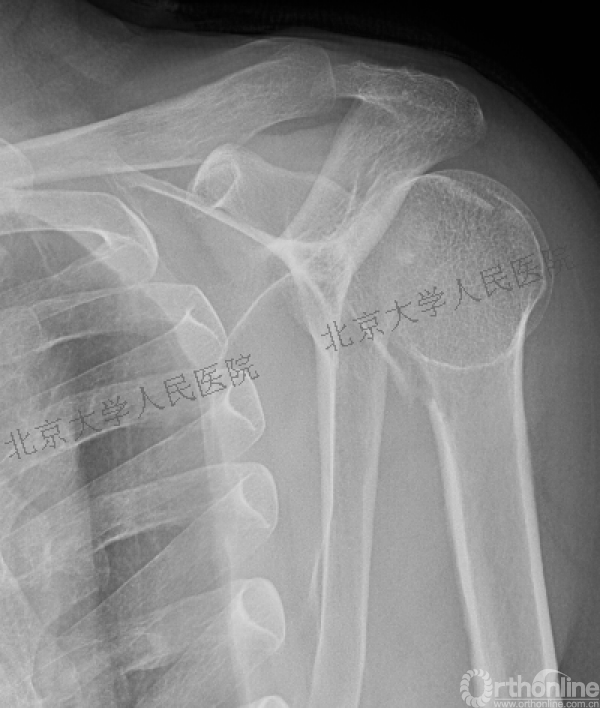

我们接诊的病人:谷××,男,61

一过性意识丧失,右肩疼痛伴活动受限14小时入院

(一)查体:右肩关节肿胀,前方空虚,喙突凸起可触及。后方饱满,可触及肱骨头。局部压痛明显,活动受限。右手拇指指尖部轻度麻木,末梢血运良好。

X线检查

(二)目前诊断:

1.右肱骨近端骨折

2.右肩关节后脱位